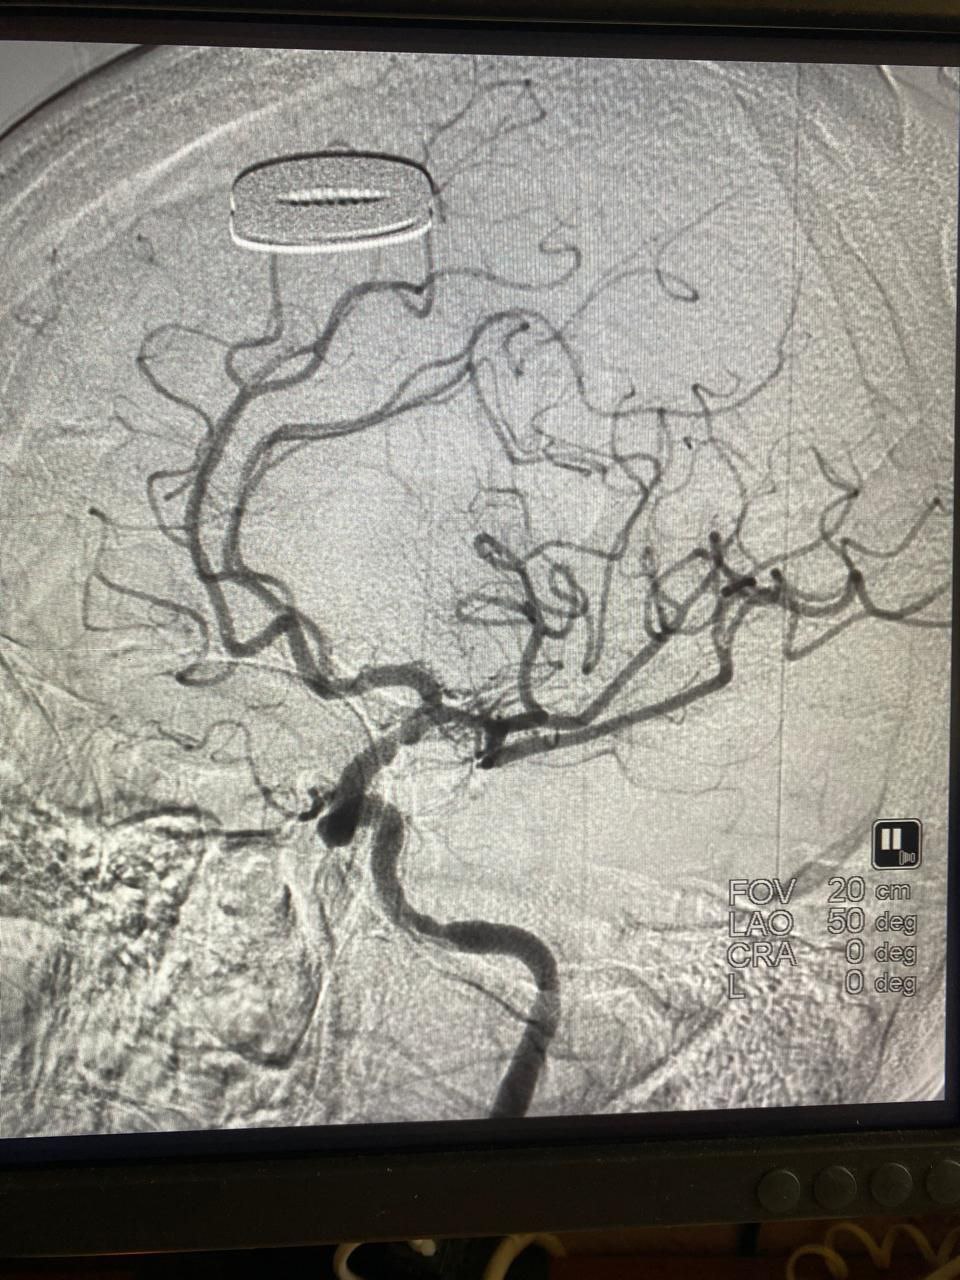

При поступлении отмечалось нарастание отрицательной неврологической динамики: парез мышц одной половины тела, потеря речи, угнетение сознания. Женщину экстренно подали в рентген-операционную, где была проведена успешная операция по удалению тромба и восстановлению мозгового кровотока.